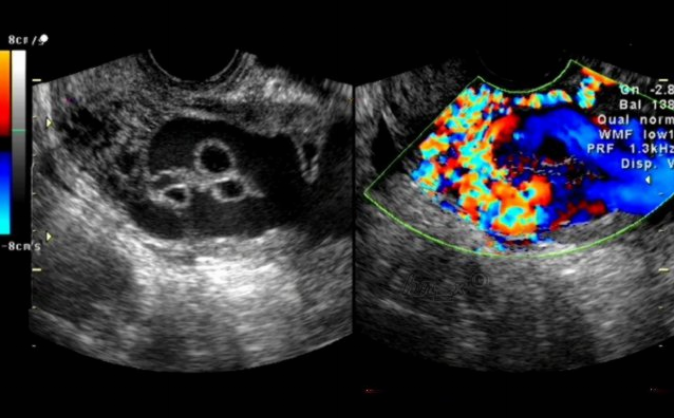

彩超不是五颜六色 为什么都是黑白的?

“经常有朋友说,大夫,我做的是彩超,为什么都是黑白的?你是不是给我做了个B超、黑白超?”何英自己说道,“彩超不是五颜六色的,这也是人们对彩超认识的一个误区,彩超可以通过红色、蓝色来显示血流的方向,而器官、组织或病灶仍以灰、白、黑的形式显示在屏幕上,如果需要观察血流情况,医生才会加上彩超功能,确定器官及病灶的血供情况、血流方向、血管是否通畅、有无狭窄闭塞等。”